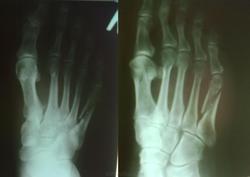

Уважаемые коллеги, вашему вниманию представляются контрольные снимки (через 1,5 месяца с момента травмы) пациента 57 лет с переломом диафиза 5 плюсневой кости. Написал: Р-признаки некоторого вторичного смещения отломков, формирования периостальной костной мозоли. Заключение: Р-признаки перелома в процессе консолидации. Есть возражения? Нет возражений?

Снимок в момент травмы

косо-поперечный перелом диафиза 5 плюсневой кости со смещением отломков до 1/2 ширины диафиза (в косой проекции), в фазе консолидации. Консолидация замедлена.

Эндостальная костная мозоль слабая, периостальная не просматривается. Через 1,5 месяца вполне можно говорить о замедленной консолидации.

Как по мне, косой перелом при наложении гипса и бинтовании имеет склонность к увеличению смещения отломков. То есть не факт, что был вторичный перелом.

А вот эта (стрелки), разве не периостальная.

Всем спасибо за высказанные мнения. Вот снимок через полгода с момента травмы.

Спасибо, Евгений. Однако, замедленно-замедленно, но срослась-таки.